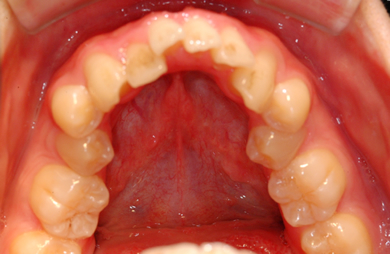

| 主訴 | 乱ぐい歯を治したい。 | ||||||||||||||||||||||||||||||||

| 治療方針 | 歯のがたつきが大きいことより上下左右第一小臼歯を抜歯して、マルチブラケット装置にて治療。また、親不知がまっすぐ生えることができず横を向いている状態なので、まっすぐにする隙間があることから親不知も使用し、矯正を行う。 | ||||||||||||||||||||||||||||||||

| 治療内容 | 唇側矯正(ホワイト) | ||||||||||||||||||||||||||||||||